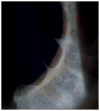

Results: Unresponsive mydriatic pupils with scalloping wisps of persistent pupillary membrane from the iris collarette were an early indicator of this rare genetic disorder in all three cases. Tortuousity of retinal arterioles was the main posterior pole finding, apparent during the first year of life and with a tendency to increase with age. In one case, it progressed to an aneurysmal-like state with breakdown of the blood-retinal barrier.